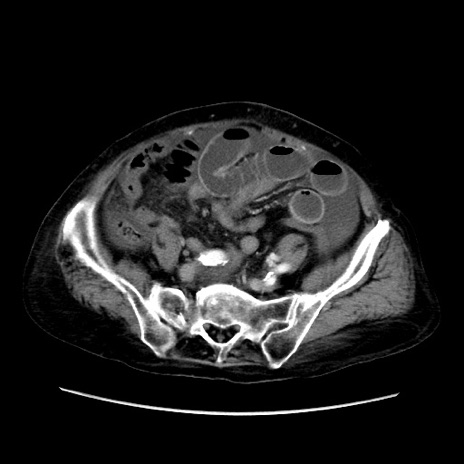

症例31(横断像)

【症例】80歳代 女性

【主訴】腹部膨満感

【現病歴】他院にて肝硬変にてフォロー中。1週間前から便秘、腹部膨満感、臍部腫瘤あり受診となる。

【既往歴】肝硬変

【身体所見】腹部膨隆あり、皮膚変化なし、疼痛なし。

【データ】WBC 4600、CRP 0.25